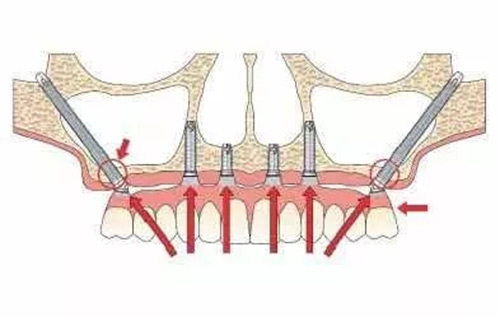

穿颧穿翼种植牙作为口腔种植领域的“技术”,专为上颌骨重度萎缩、骨量不足的患者设计。这项技术通过将种植体植入颧骨或翼板骨,实现“无土栽培”般的稳固结果,但价格也因技术难度和材料成本较高。